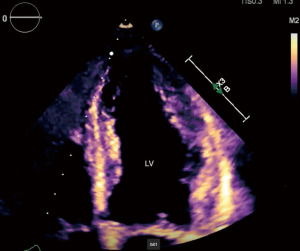

A 63-year-old woman with a medical history significant for stage IV lung adenocarcinoma with brain metastases, atrial fibrillation, peripheral artery disease, and deep vein thrombosis (DVT) on Apixaban, presented to the hospital with a 1-week history of nausea, vomiting, chest pain, and intermittent shortness of breath. She described the chest pain as pressure-like, localized to the lower chest, and denied orthopnea, paroxysmal nocturnal dyspnea (PND), or lower extremity swelling. On physical examination, she appeared mildly distressed and diaphoretic. Heart and lung auscultation were unremarkable. ECG revealed a new right bundle branch block (RBBB) without ST-segment elevation or depression. The cardiac monitor showed supraventricular tachycardia with a heart rate of 150 bpm. Laboratory investigations showed elevated troponin (938 ng/L), creatinine (1.29 mg/dL), and C-reactive protein (CRP) (219 mg/L). Chest computed tomography (CT) scan ruled out pulmonary embolism (PE). The patient was started on heparin infusion for possible acute coronary syndrome and received adenosine and intravenous metoprolol which normalized her heart rate. Transthoracic echocardiogram (TTE) revealed normal LV size and thickness but mildly decreased LV systolic function with apical ballooning consistent with Takotsubo cardiomyopathy (Figure 1, Video 1). Left heart catheterization (LHC) ruled out obstructive disease (Figure 2), leading to the cessation of ACS treatment, and the patient was discharged.